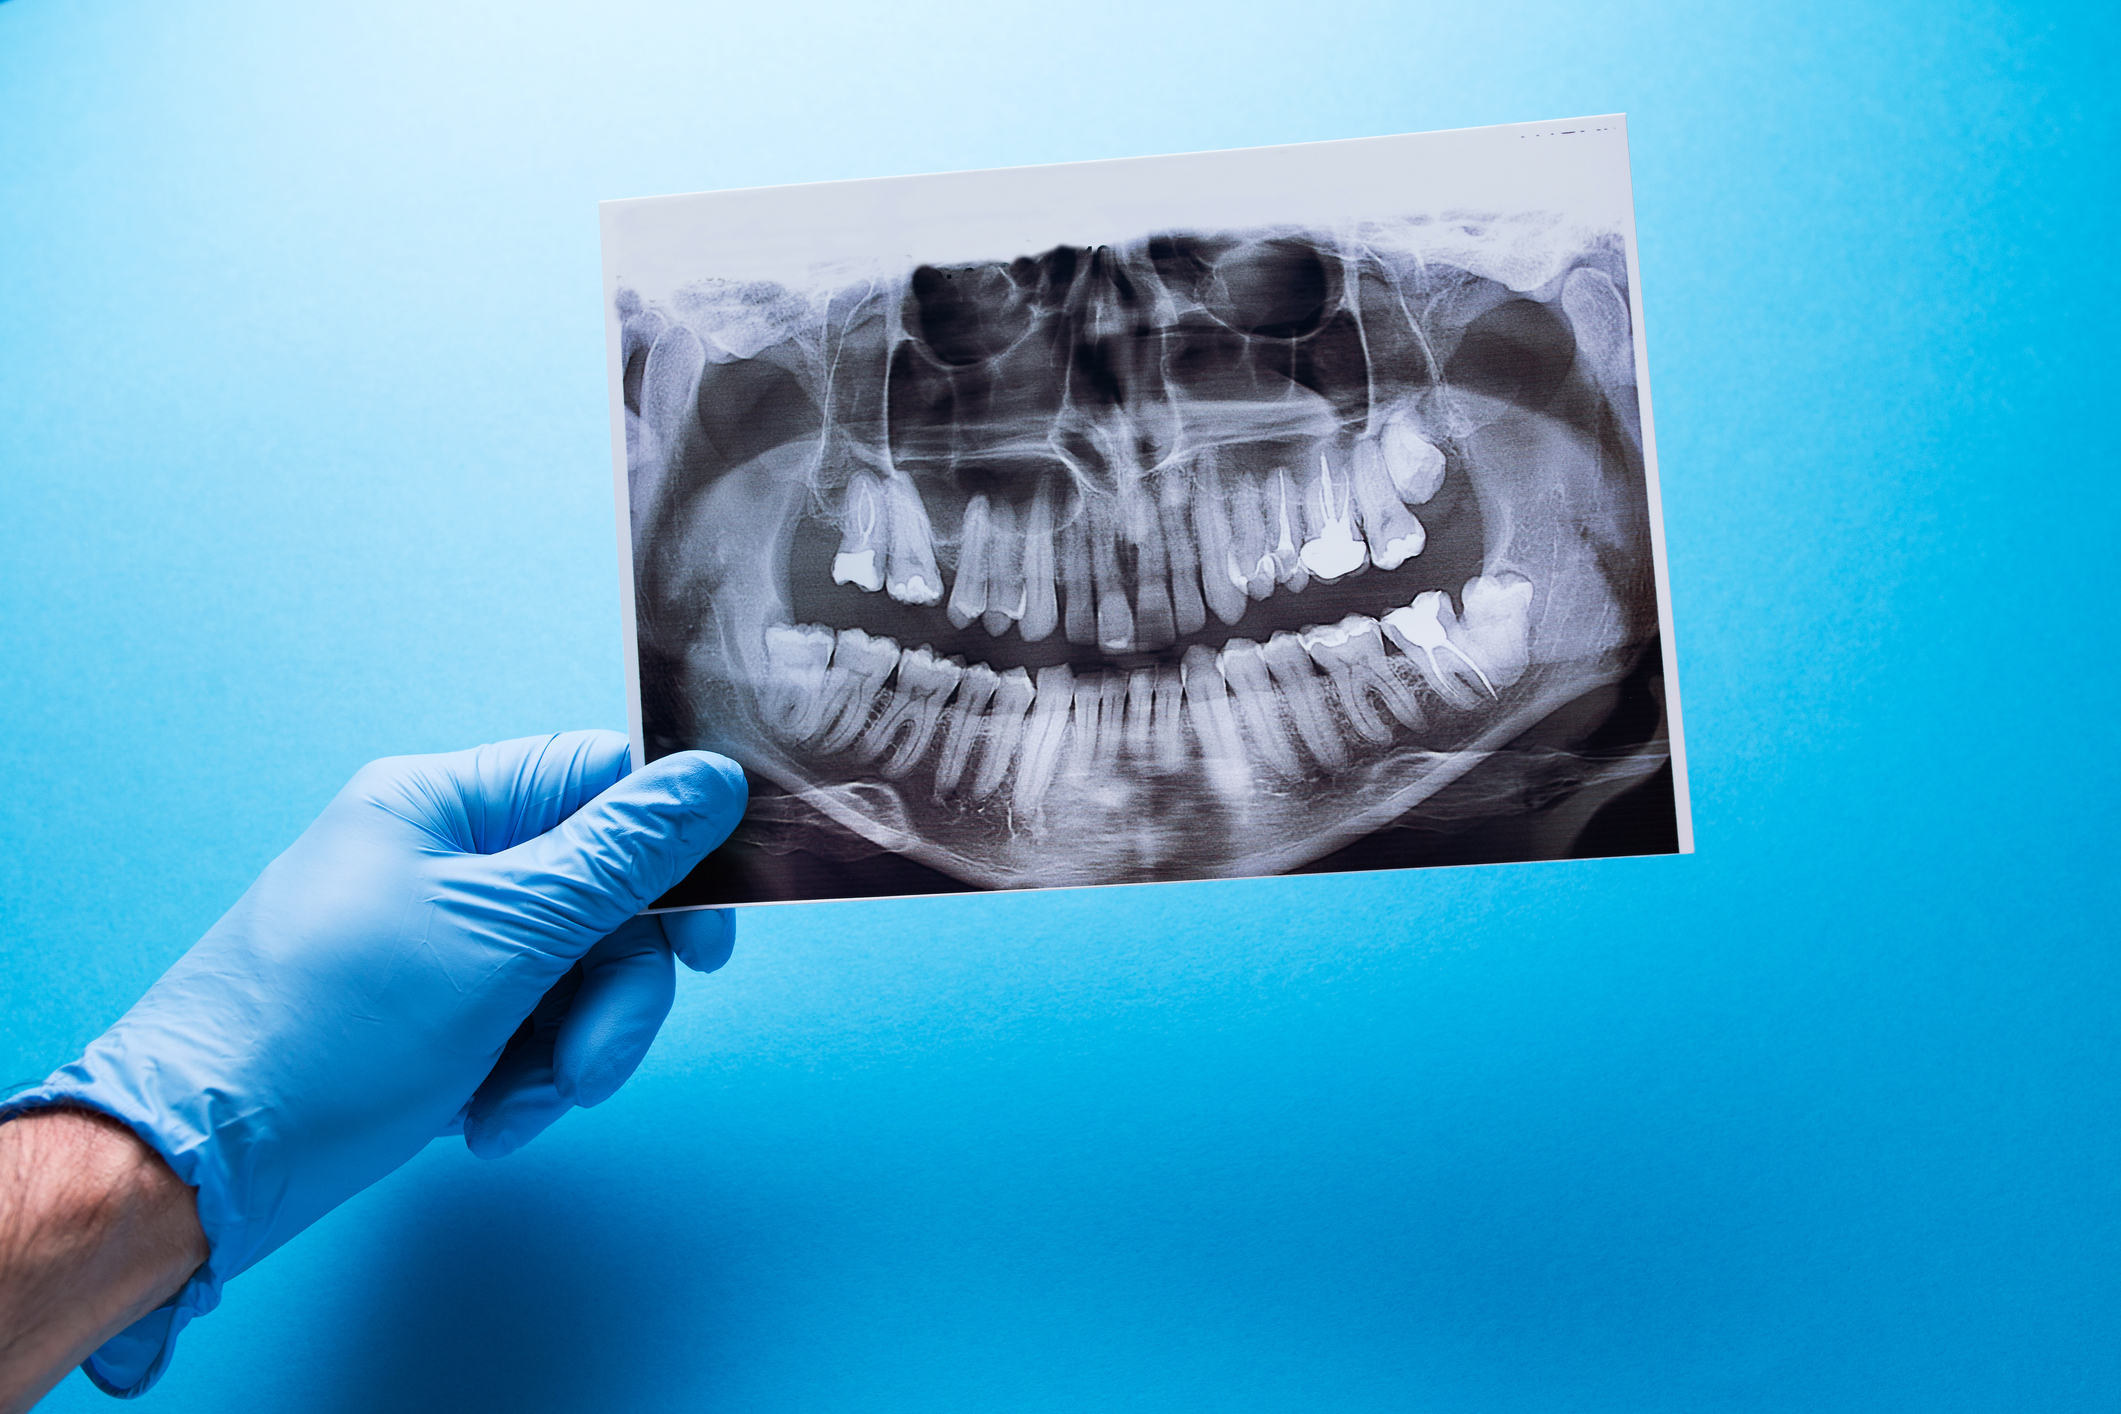

Ortopan

Ortopantomogram oz. panoramski posnetek je najpogostejše ekstraoralno slikanje zob in kosti spodnjega dela obraza v dentalni medicini.